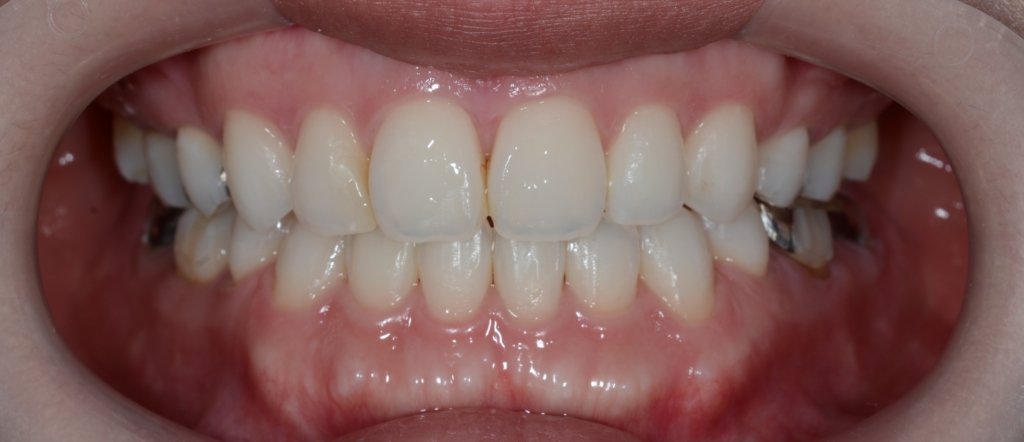

【After】

横顔や口元は患者さんの希望通りにスッキリして、満足してもらえました。

術前も口元にEラインを引くことが出来ました(レントゲン参照)が、お顔全体のバランスという意味で、同じEラインであっても術前と術後ではスッキリ感が異なります。

なお結局、ガミースマイルの改善は行わないまま治療を終了しました。

最後に、矯正治療前後のと「口元の写真」「レントゲン写真」「歯並び」の比較をお見せしましょう。

口元が飛び出た感じも無くなりました

お口を閉じた時のオトガイ部のシワも、治療後は無くなりました